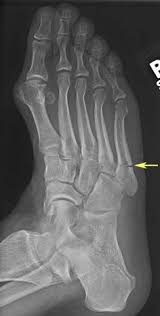

Intramedullary Screw Fixation Of Proximal Fifth Metatarsal Fractures In Athletes from www.scielo.br Lengthy healing times and risk of refracture may be reasons for surgical repair in these fractures. A foot can be broken in many places learn about the jones fracture, what types of treatments are available, and if jones fracture surgery is the best treatment option. Patient may be in a removable boot after surgery for a week or two at the direction of the physician. Jones fractures are named after sir robert jonestrusted source , an orthopedic surgeon who in 1902 reported on his own injury and the injuries of several people he. Do you have a jones fracture of the 5th metatarsal? Jones fracture surgery recovery on mainkeys. A jones fracture is a break between the base and middle part of the fifth metatarsal of the foot. Yet surgery is not always necessary.

A jones fracture is a break between the base and middle part of the fifth metatarsal of the foot. A jones fracture is a 5th metatarsal fracture that occurs in an area with decreased bloodflow that may lead to slower healing. Remember that below is a guide to recovery and that everyone heals at different rates and some people do take longer. Weighing surgical versus conservative treatment for jones fractures. Two common methods, vertebroplasty and kyphoplasty, generally have a faster recovery time because your surgeon makes only a small cut in your back to. Zone 2 fractures are known as jones fractures. Well find out exactly how to get this bone feeling better! Have foot pain at some time in their lives. What is a lisfranc fracture? Jones fracture surgery recovery on mainkeys. This is another way of saying a jones fracture. Sanders type 3 break with surgery about 1 week later. It can take time to heal because there is limited blood flow to the area.

Fifth Metatarsal Fracture from geominesbtp.e-monsite.com I went in to the doc yesterday. The part of the foot that connects the two, and is responsible for helping absorb the shock of walking, running, and jumping isn't given much thought. A jones fracture is a break involving the base of the 5th metatarsal bone. I recommend that you consult your surgeon about the specifics of your recovery as. About 75% of people in the u.s. A foot can be broken in many places learn about the jones fracture, what types of treatments are available, and if jones fracture surgery is the best treatment option. A jones fracture is a break between the base and middle part of the fifth metatarsal of the foot. You should be able to return to most activities in about six months.